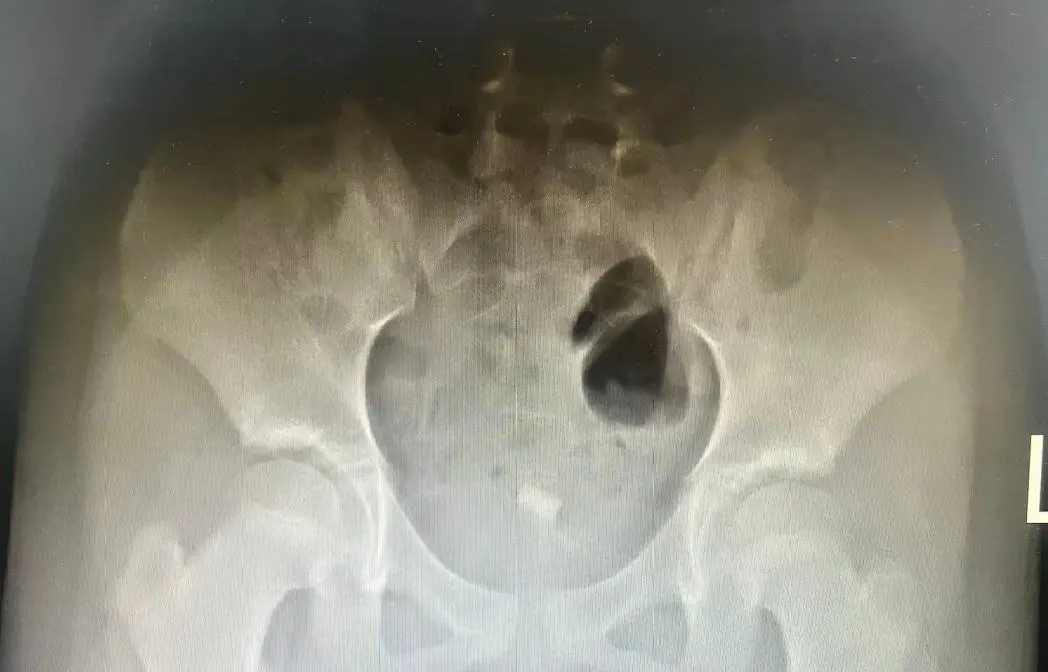

当天玲玲做完影像学回报结果提示盆腔内存在伪影,是异物?

为进一步确认是伪影抑或异物可能,再次完善盆腔核磁MRI,所得结果令人颇为震惊:阴道内异常信号并伪影,考虑异物可能!如同一块巨石投入平静的湖面,激起了层层涟漪。

术中,医师们凭借凭借着娴熟的手法,首先取出了3根直径约0.8cm-3.5cm铅笔内心,紧接着是一块橡皮,它虽然体积稍大,但由于在患儿体内停留时间较长,已经变得异常粘稠,给手术增加了不小的难度。

最终,在医护人员共同努力下,从玲玲私处内取出三根铅笔内芯、一块橡皮以及九块毛絮组织。经过精心治疗与护理,目前患儿已康复出院。